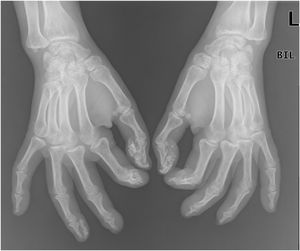

A 50-year-old woman with limited SSc, evolving over 19-years, referred stiffness, pain and ulceration on the first four digital pulps of each hand for one year. She underwent surgical excision of calcium deposits of the 2nd and 3rd fingers bilaterally and started diltiazem 90 mg/day. For two years, there was symptomatic progression. Skin involvement also included sclerodactyly and malar cutaneous telangiectasia. In addition, her SSc was complicated by oesophageal dysmotility, partially controlled with proton pump inhibitors, and severe Raynaud phenomenon (RF), under bosentan. No evidence of pulmonary arterial hypertension or other systemic involvement. Laboratory tests were positive for Antinuclear antibodies (ANA) and anticentromere antibodies (ACA). Physical examination revealed painful, stiff, skin-coloured papules, 4‒10 mm, distributed on the pulp of the 1st, 2nd and 4th right fingers and the 1st left finger, compatible with CC (Fig. 1), as confirmed by hand radiography (Fig. 2). Intralesional STS treatment was proposed due to significant morbidity, progression under diltiazem and the involved site. The procedure was performed using an aseptic technique and under digital nerve block, with a 250 mg/mL solution. Depending on the size of the lesion and pulp distensibility, 0.1‒1 mL of STS solution was injected into the base of the calcifications. Initially, at a 6 to 8-week interval, and after improvement, every 3-months. 25 sessions were performed in 5-years, with continuous symptomatic improvement and better functional status. Hand radiography confirmed a sustained reduction in calcification size (Fig. 3). During the first 2-years, episodes of ulceration and spontaneous drainage of liquified calcium deposits were reported, both self-limited. Additionally, 2 local infections were treated with oral antibiotics. There were no systemic adverse events or analytical abnormalities. However, 2 weeks after the last administration, the patient developed necrosis on the pulp of the 1st right and 2nd left fingers. Treatment with bosentan was suspended 3-months earlier due to long-term control of RF. Oedema from STS infiltration may have triggered a more pronounced RF episode, leading to pulp necrosis. The patient underwent treatment with iloprost 0.4 ng/Kg/min for 3-days and resumed bosentan, with complete healing. Currently, she is asymptomatic, with residual calcifications in hand radiography.